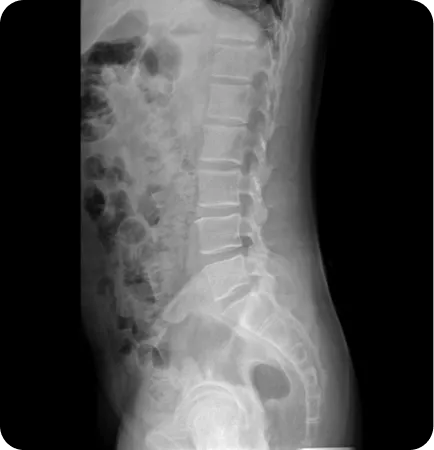

허리 통증

골반은 허리와 연결되어 있어 골반 틀어짐은 요통을 유발하고 디스크탈출증 후관절증후군 척추관협착증 천추분리증 척추전방전위증등 다양한 척추문제의 원인이 됩니다.

고관절 통증

사타구니쪽의 서혜부 통증이나 엉덩이 옆쪽의 통증등을 유발하고 고관절에서 뚝뚝 하는 소리가 나기도 합니다.

천장관절증후군

양쪽 골반을 연결하는 천골과 골반뼈 사이관절 주변의 인대 약화로 인해 허리와 엉덩이 주변에 통증이 나타나는 질환입니다. 특히 양반다리 자세가 어렵습니다.